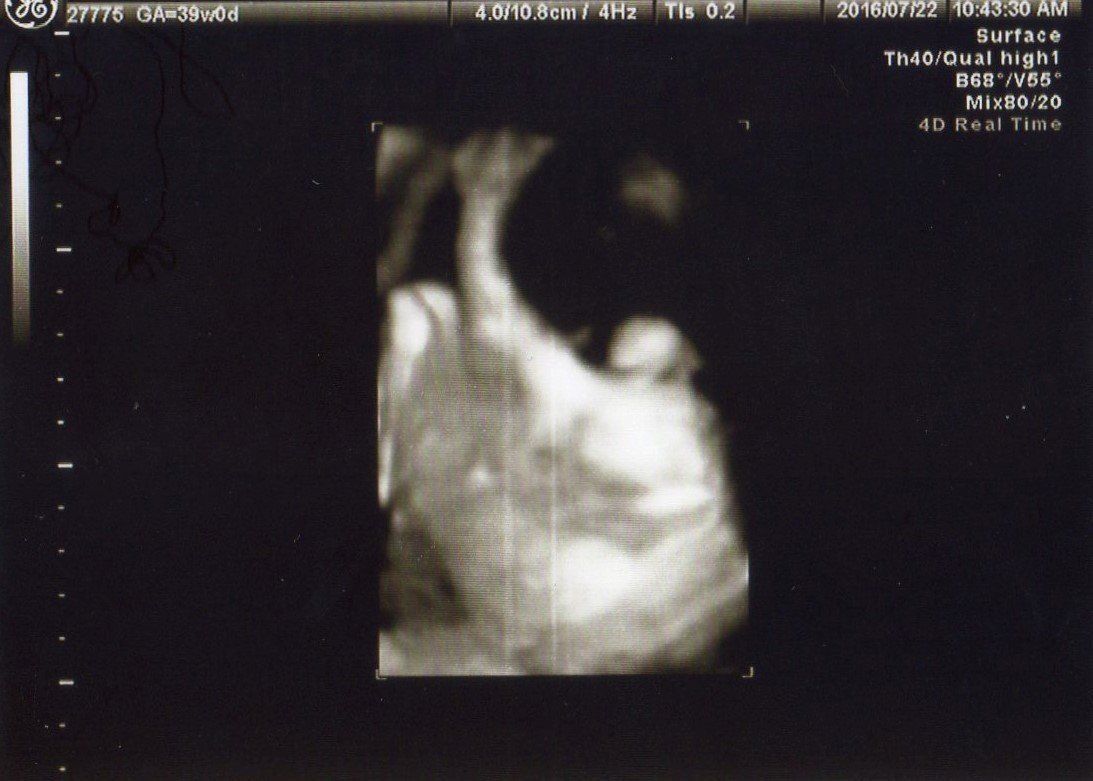

これも妊娠39週目の同じ日の別写真で、体の下部から撮った写真です。

この頃は赤ちゃんが夜動いて寝付けないこともありましたが、おなかの中でのびのびと過ごしてくれていることは幸せなこと!

好きな音楽を聴いたり、温かい飲み物を飲んだりして乗り切りました。